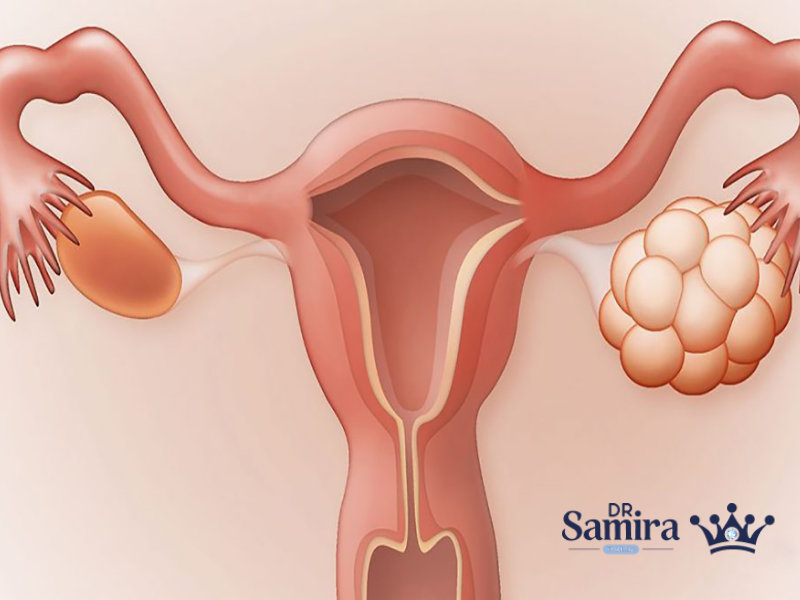

درمان سرطان تخمدان ترکیبی از تصمیمهای تخصصی، شواهد علمی و شرایط فردی بیمار است. اگرچه بسیاری...

- ۲۰ آگوست ۲۰۲۵